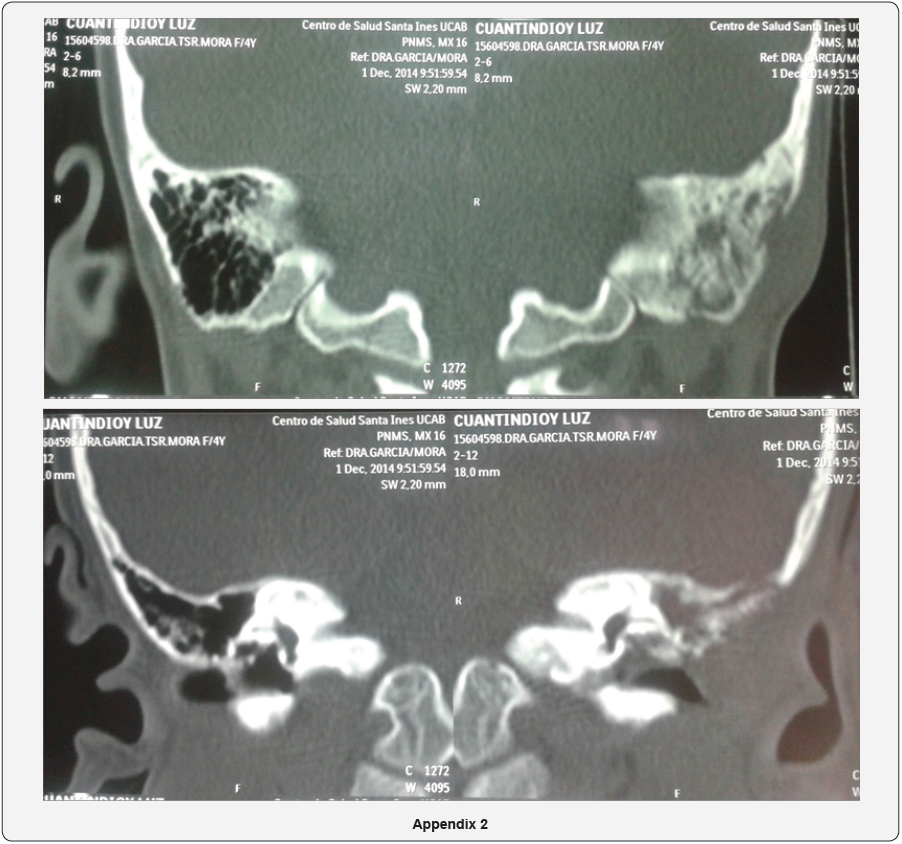

- 03/12/2014: Tomography of the middle ear and mastoid is received: evidencing mastoid asymmetry, loss of the cortical mastoid of the left ear that impresses secondary to an erosive - infiltrative type process that compromises the superficial mastoid ipsilateral cells. Obliteration of the left external auditory canal at the expense of volume increase at the ceiling level, isodense characteristics, occupation of antrum, epitympanum and mesotympanum by soft tissue density, with preservation of ossicular elements and thickening of the left tympanic membrane (Appendix 2).